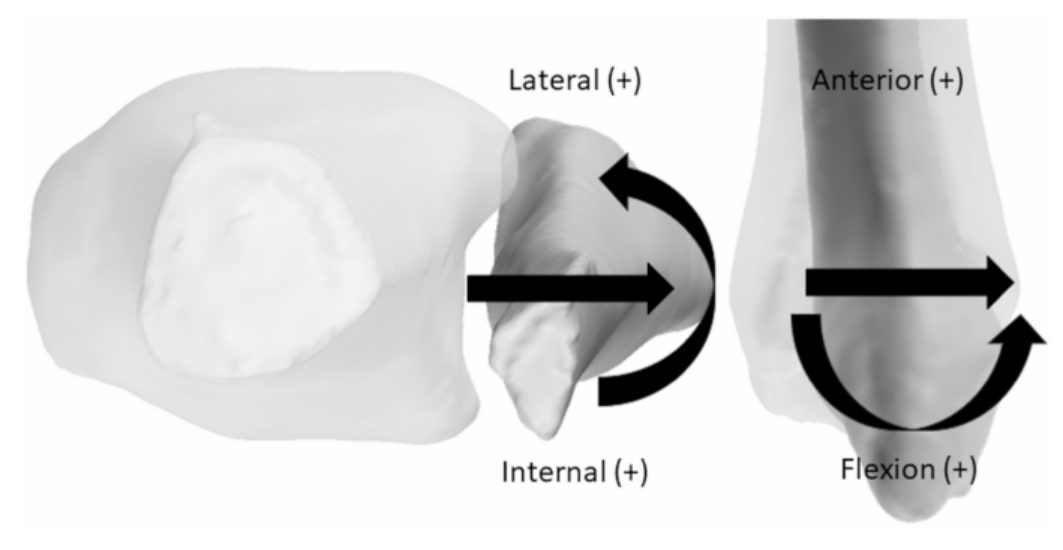

Рис. 11. Вектор движений малоберцовой кости в синдесмозе

Относительное движение в синдесмозе зависит от положения стопы и характера нагрузки. При переходе от подошвенного к тыльному сгибанию малоберцовая кость совершает 1,25 мм латеральной трансляции и 2° наружной ротации.